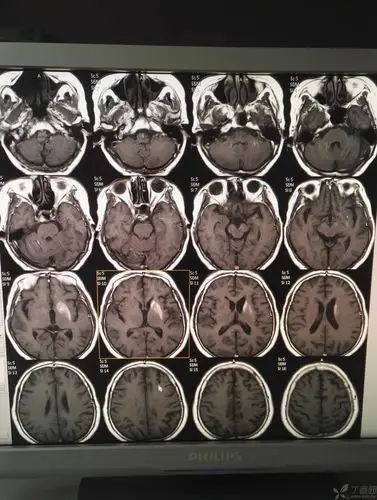

左侧基底节区普遍高密度影是什么呢 - 影像医学和核医学讨论版

两侧基底节区信号如图,患者有高热,考虑脑炎?基底节区脑炎常见吗?